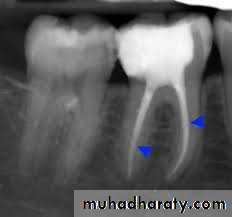

Primary infections are characterized by a mixed (multispecies) community conspicuously dominated by anaerobic bacteria. The number of bacterial cells may vary from 10³ to 10⁸ per root canal with a mean of 10 to 20 species/phylotypes per infected canalThe size of apical periodontitis lesion has been shown to be proportional to the number of bacterial species and cells in

the root canal the number of taxa per canal (is a group of one or more populations of an organism) was clearly in direct proportion to the lesion size: small lesions ( < 5 mm) harbored about 12 taxa, lesions from 5 to less than 10 mm harbored 16 taxa, and lesions over 10 mm harbored about 20 species. Some canals associated with large lesions may harbor even more than 40 taxa

Symptomatic apical periodontitis and acute apical abscesses

Symptomatic apical periodontitis and acute apical abscesses are typical examples of endodontic infections causing severe symptoms. In these cases, the infection is located in the canal, but it has also reached the periradicular tissues and, in abscessed cases, can spread to other anatomic spaces The microbiota involved in endodontic abscesses is mixed and dominated by anaerobic bacteria.Direct comparisons using molecular technology reveal an average of 12 to 18 taxa per abscess case, compared with 7 to 12 taxa present in root canals of teeth with asymptomatic lesions